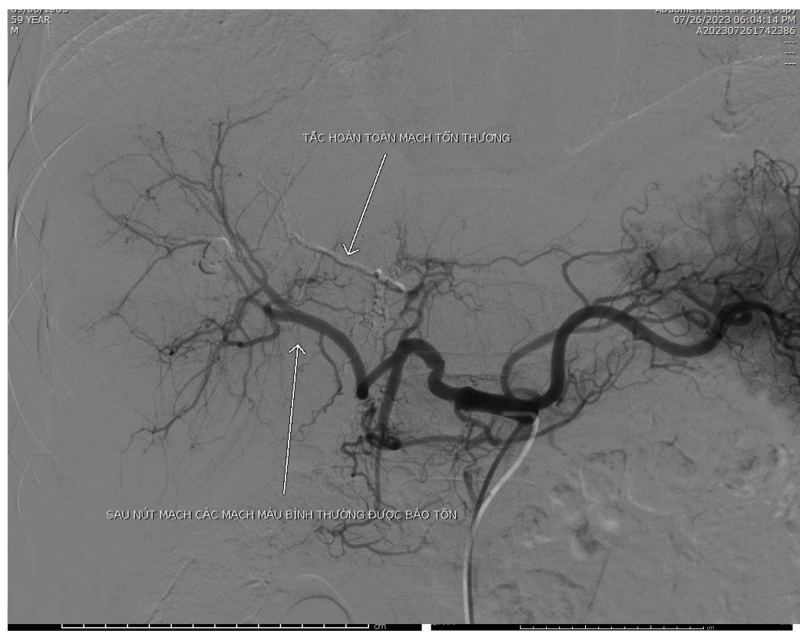

Hình ảnh sau can thiệp.

Với hệ thống máy chụp mạch

máu số hóa xóa nền (DSA), kíp can thiệp do Bs.CKI Lê Tiến Hưng, Trưởng Đơn

Nguyên điện quang - can thiệp, Bệnh viện Bãi Cháy đã tiến hành can thiệp nút

mạch thành công cho bệnh nhân sau gần 1 tiếng đồng hồ, giúp cầm máu nhanh chóng

cho bệnh nhân.

Hiện tại, sau 1 ngày can thiệp sức khỏe bệnh nhân đã tiến triển tốt, mạch, huyết áp ổn định.